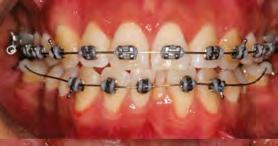

52 | SONRIENDO AL FUTURO

Tratamiento ortodóncico en paciente adulto tratado con extracciones de primeros molares permanentes. Reporte de caso

en paciente adulto tratado con extracciones de primeros molares permanentes. Reporte de caso

Dentista y Paciente 52 Sonriendo al futuro